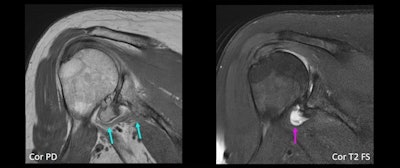

Coronal MR images of a 66-year-old woman show definite small AIGM (blue arrows), corresponding to diagnostic confidence of 4. There is also high-grade glenohumeral osteoarthrosis, as well as small joint effusion (purple arrow).ARRS